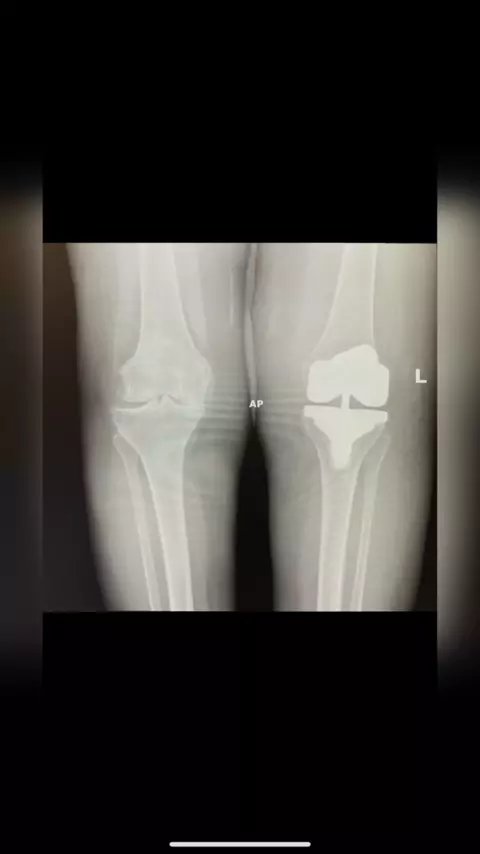

Before & After Robotic Knee Replacement πŸ”₯πŸ¦ΎπŸ‘¨πŸ½β€βš•οΈ#orthopedicsurgeon#kneesurgery#kneepain#kneereplacement#hipsurgery#hippain#hipreplacement#surgeon#doctor#RN# More